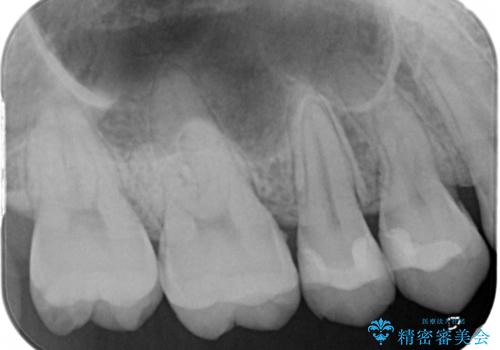

- 他県より引っ越しをされたため、途中になってしまっている虫歯治療の続きをしてほしいと来院された患者様です。

痛み等の自覚症状はありませんでしたが、広範囲にわたる虫歯を認めたため、セラミッククラウンによる治療を行いました。

奥の歯は歯ブラシが届きづらく、気づかないうちにプラークが蓄積して虫歯の発生源となっていることがあります。

今回のケースでは、一番奥の歯の後ろ側に向かって虫歯が進行していました。一番奥の歯は元々の歯の高さが低いことが多く、被せ物が割れるリスクが増加したり、被せ物が外れやすくなる場合があります。歯牙切削量の少ないゴールドアンレーもご提案しましたが、セラミックをご希望されたため、今回はクラウンによる治療を行いました。